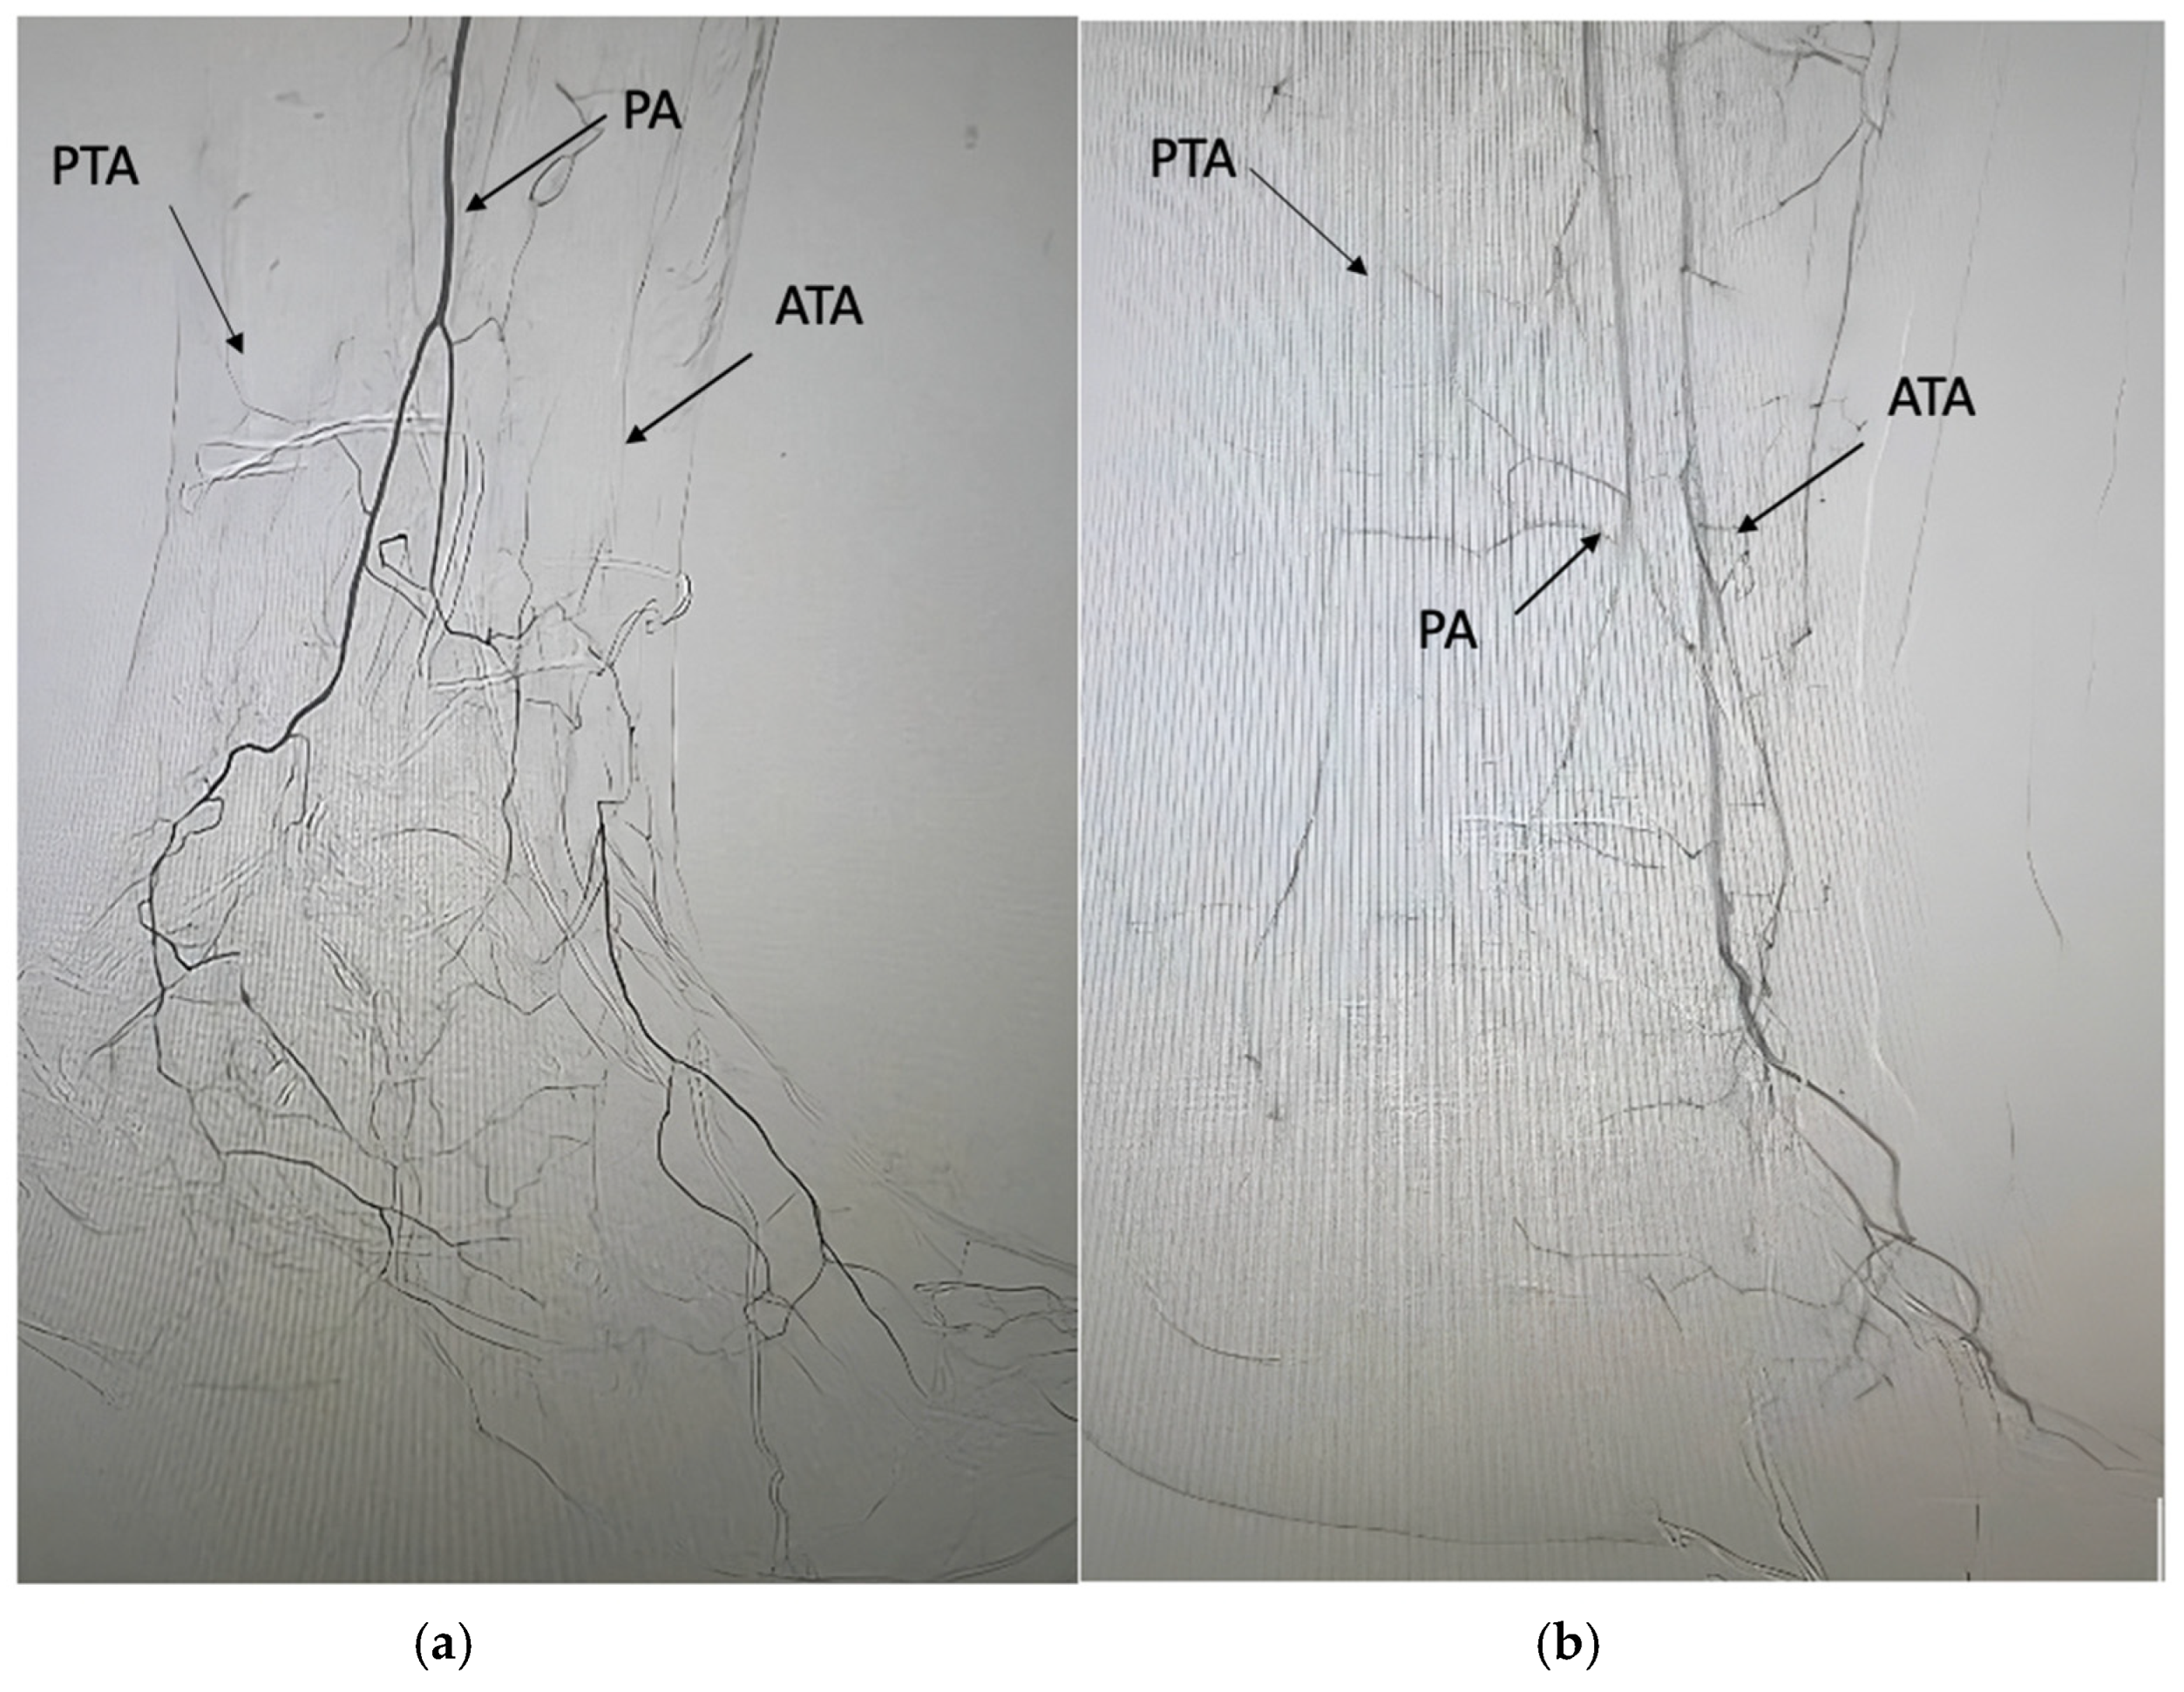

- Ferraresi, R.; Mauri, G.; Losurdo, F.; Troisi, N.; Brancaccio, D.; Caravaggi, C.; Neri, L. BAD transmission and SAD distribution: A new scenario for critical limb ischemia. J. Cardiovasc. Surg. 2018, 59, 655–664. [Google Scholar] [CrossRef] [PubMed]

- Meloni, M.; Izzo, V.; Giurato, L.; Gandini, R.; Uccioli, L. Below-the-ankle arterial disease severely impairs the outcomes of diabetic patients with ischemic foot ulcers. Diabetes Res. Clin. Pract. 2019, 152, 9–15. [Google Scholar] [CrossRef] [PubMed]